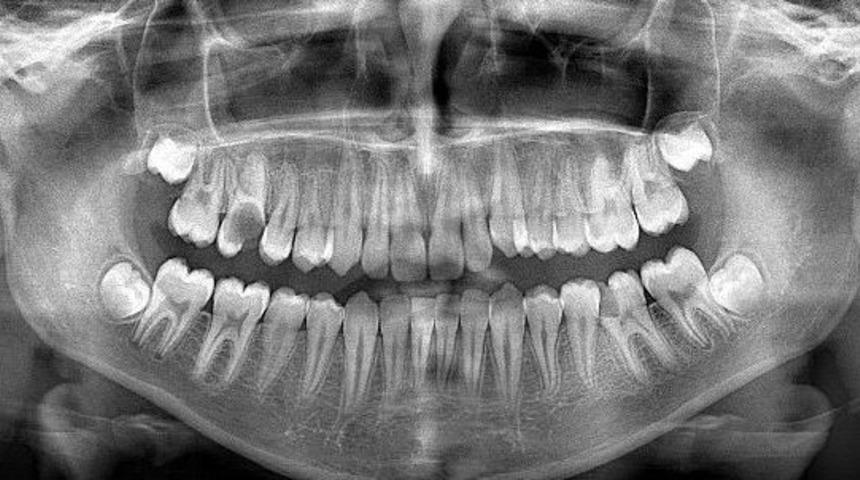

Bursa’nın Yenişehir ilçesine son teknoloji kullanılarak yeni, Ağız ve Diş Sağlığı Merkezi yapılması için çalışmalara başlandı.Konuyla ilgili açıklama yapan AK Parti ilçe başkanı Adnan Kamıl, "TOKİ konutlarının olduğu bölgede 2 dönüm toplam alanı olan 1200 metre kapalı alan üzerine Ağız ve Diş Sağlığı Merkezi yapılıyor. Yapılacak yeni yer ile artık halkımız İnegöl’e ve diğer yerlere gitmekten kurtulacak. Burada son teknoloji kullanılacak olup, panoramik röntgen cihazları ile ağız ve diş yapısının tamamının filmleri çekilip ona göre anında müdahale edilecek diye konuştu.Başkan Kamıl, “Yeni yapılacak Ağız ve Diş Sağlığı Merkezinde 10 doktor hizmet verecek. Şimdi mevcut hastanemizde 4 koltuk bulunuyor. Mevcut yerde yerimiz dar yeni hizmete girecek binamızda her şey en üst standartlarda olacak. Çevre düzenlemesi yapılan diş hastanemiz 2017 yılının yaz aylarında hizmete girecek” dedi.